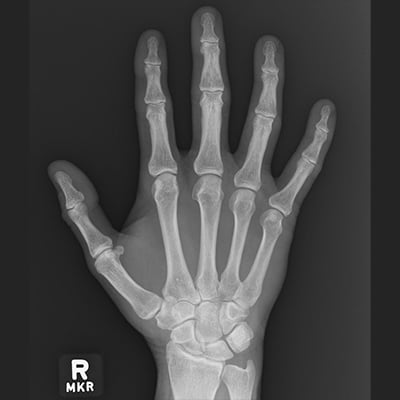

This module will help you achieve optimal images of the thumb and fingers, hand, wrist, and forearm. Patient positioning, technical settings, and patient instructions are discussed. Descriptions and images of the expected anatomical structures are included, as well as image evaluation criteria.